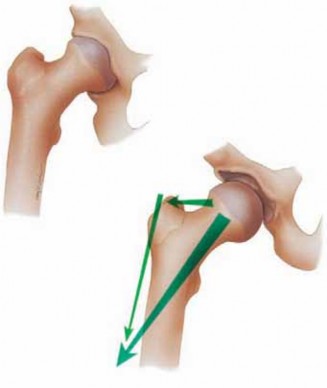

7.

Femoroacetabular impingement (both pincer and cam type) has been recognized as a causative factor in the development of soft tissue joint damage.14 It is the soft tissue damage that then becomes symptomatic, necessitating treatment.

1.

Pincer impingement is associated primarily with labral pathology due to excessive compression and then secondary development of articular breakdown ( FIG 2A).

2.

Cam impingement is associated with selective articular delamination of the anterolateral acetabulum with a variable amount of associated labral pathology ( FIG 2B).

A B ### FIG 2 • A. Pincer impingement: mechanism of labral breakdown. B. Cam impingement: mechanism of articular delamination.